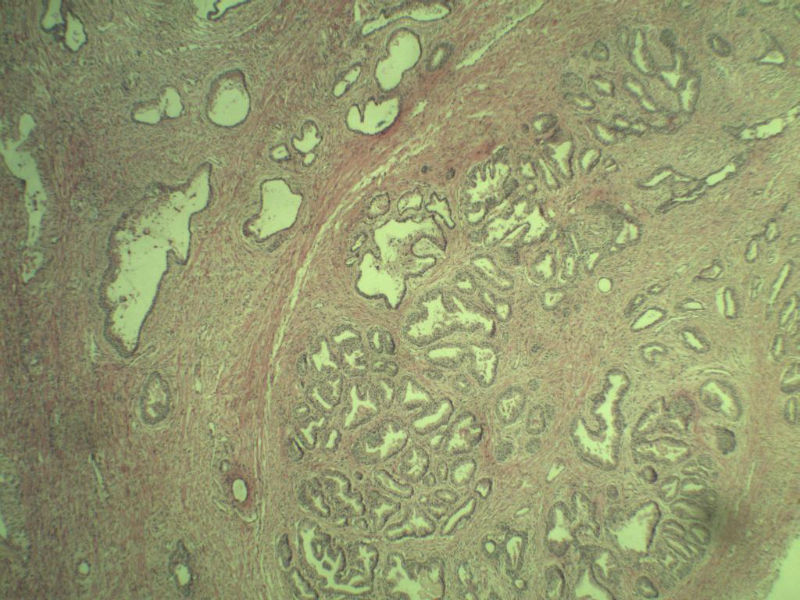

男 75岁 因排尿困难半年行前列腺切除术,体积 4 × 3 × 2.5 cm3,切面灰白,实性,质韧。请各位老师看看 有问题没? 谢谢了!

良性前列腺增生伴尿路上皮化生

前列腺增生症伴鳞化

前列腺增生伴尿路上皮鳞化及Brown巢形成,未见恶性。

前列腺增生,有腺瘤样结节形成。